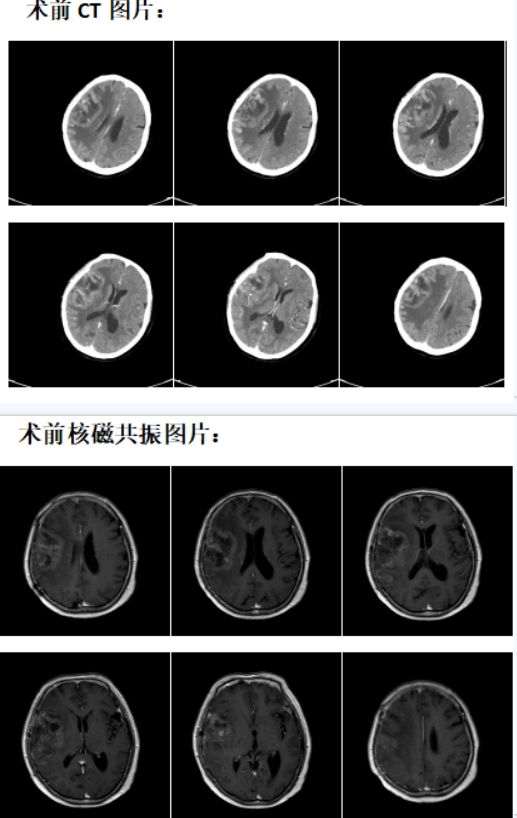

近日,淄博市第四人民医院放射科宓兵团队成功为一位脑胶质母瘤术后复发患者实施CT引导下的粒子治疗。

患者女,64岁,脑胶质母瘤术后复发,放疗后5个月,左侧肢体活动不利加重一个月。

胶质瘤是成人最常见的颅脑原发性肿瘤,星形细胞瘤好发于青壮年,胶质母瘤多见于中老年,恶性程度非常高,最常见的症状包括颅内压增高、神经功能障碍和癫痫发作。治疗以手术切除为主,但术后残留常见,术后短期容易复发,复发肿瘤以放化疗为主,但肿瘤对外放疗敏感性不高,控制往往不理想。

影像引导下的放射性粒子植入则可以到达局部根治性效果。一般外放疗的放射剂量为50-80GY,达不到肿瘤根治剂量,而放射性粒子植入治疗是将放射性粒子植入肿瘤内部进行近距离照射,肿瘤区域的放射剂量可达150-180GY,周围正常脑组织不受照射,适形度极好,疗效可以得到保证,所以成为无法手术,不适合手术及术后复发的胶质瘤患者治疗的重要手段。